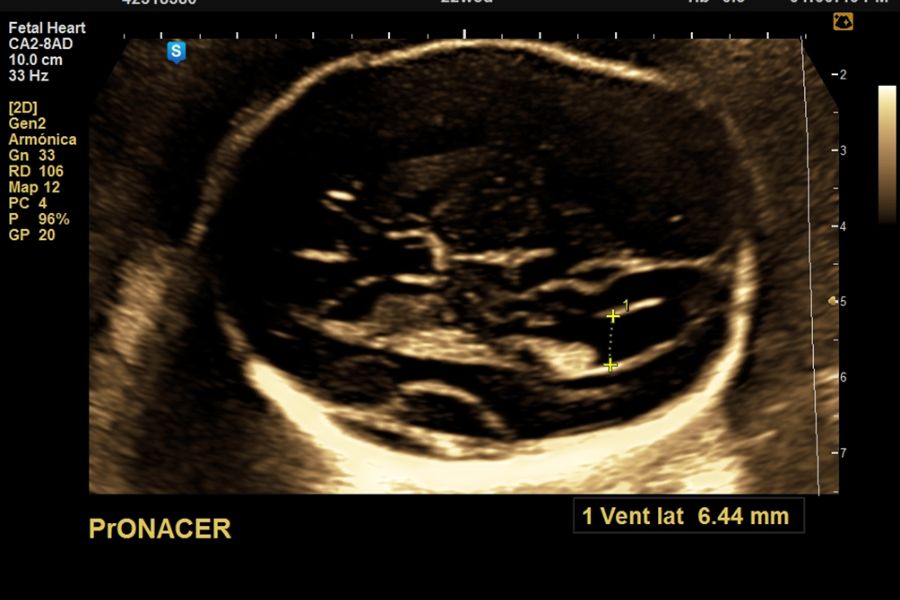

El momento óptimo para realizar el estudio ecográfico para cronicidad y animosidad es el 1er trimestre a partir de la semana 7, 11 a 14 con una sensibilidad > 98%, con una precisión menor pero aceptable en el segundo trimestre temprano (sensibilidad 90%).